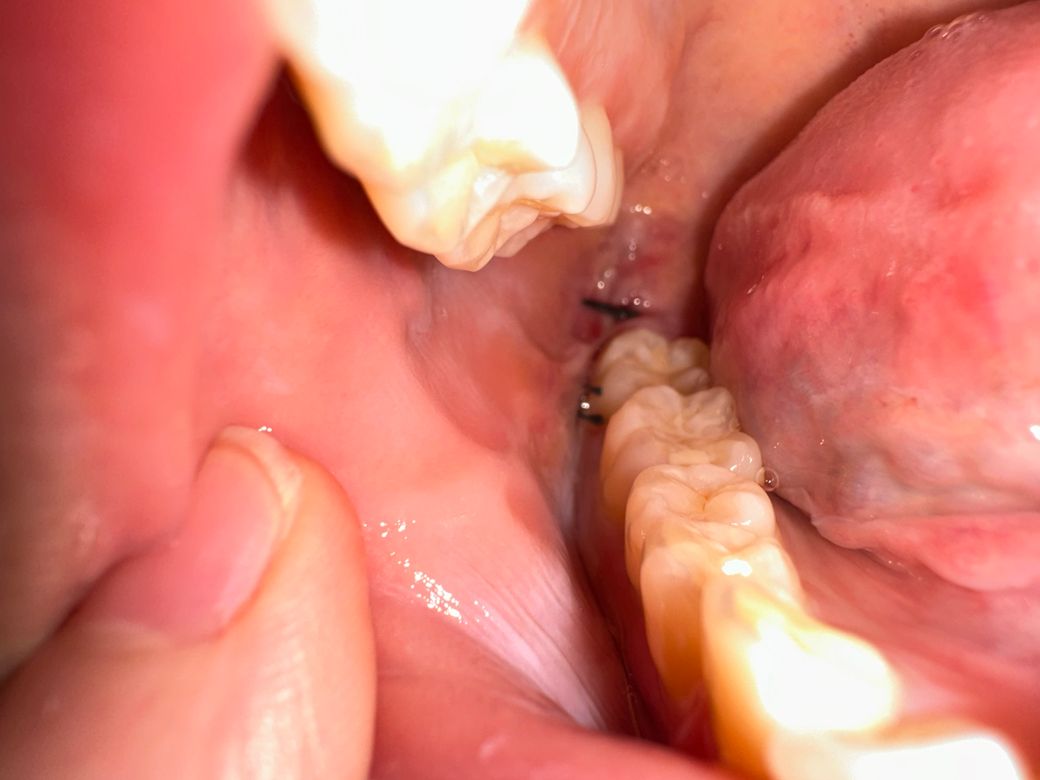

지금 뽑은지는 4일차입니다 이런 상태인데 잘 아물고 있는지 모르겠고 사람들마다 원래 실밥은 좀 다르나요 ?̊̈ 제 실밥만 이런가 싶어서요 잘 아물고 있는지 드라이소켓은 없는지 궁금합니더 지금 현재 좀 염증이 차있어거 턱이랑 볼쪽이 멍울처럼 딱딱하고 많이 부어있어요 ㅠㅠㅠ 괜찮은거겠죠? 치과에 가서 염증이 차있다고 하면 뭐 치료법이 따로 있나요? 입이 잘 안벌려지는건 염증때문일까요

봉합상태도 굉장히 좋고 염증소견도 없어보입니다.

발치후에 많이 붓고 아플 수 있는데요 때에따라 환자분처럼 입이 안벌어지기도 하지만 대부분 실밥을 풀 때 쯤에는 많이 호전이 됩니다.

그리고 발치후에 볼쪽을 눌러봤을때 덩어리처럼 단단한게 만져지는 경우도 있는데 상처가 나면 흉터가 생기는 것 처럼 안쪽에도 흉터가 생겨서 그렇다고 생각하시면 되는데요. 보통 시간이 지나면 점차 옅어집니다.